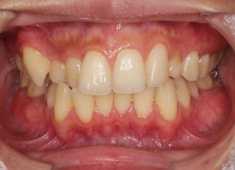

治療前

治療開始時